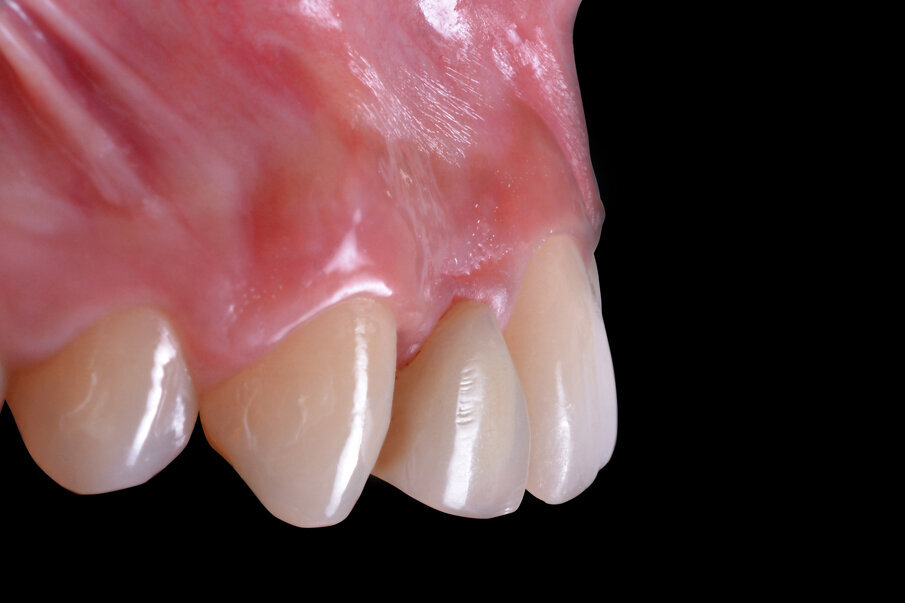

Con lo scopo di escludere controindicazioni assolute o relative alla terapia implantologica, lo studio del caso si basa sull’esame anamnestico. Nel caso specifico considerato di seguito, la paziente di anni 23 è classificabile nella categoria ASA I; all’esame obiettivo si evidenzia una mono-edentulia nel sito 1.2 a causa di un’agenesia trattata in passato con una terapia ortodontica di riallineamento dentario e di riapertura dello spazio protesico, spazio mantenuto con un Maryland bridge confezionato in resina acrilica. Un sondaggio parodontale della regione interessata permette di escludere lesioni parodontali ed evidenzia uno stato di buona salute dei tessuti duri e molli.

Gli esami radiografici completano l’approccio diagnostico iniziale e lo studio delle radiografie endorali del gruppo frontale, di un’ortopantomografia delle arcate dentarie e di una CBCT permettono di evidenziare un corretto allineamento radicolare degli elementi dentari contigui all’edentulia da trattare e una moderata atrofia orizzontale della cresta alveolare edentula (Fig. 1). Trattandosi di una riabilitazione del settore frontale è opportuno realizzare una dettagliata analisi estetica supportata da un esame fotografico corredato di fotografie extraorali (del volto e del sorriso), fotografie intraorali e da una ceratura diagnostica. L’attenzione iniziale è rivolta principalmente all’analisi dei tessuti molli e degli elementi dentari; in particolare, nel caso descritto, la paziente non presenta fattori estetici sfavorevoli dal momento che si riscontra la presenza di una linea del sorriso media, elementi dentari in area estetica sani e non discromici, fenotipo gengivale spesso, simmetria della festonatura gengivale e buona rappresentazione delle papille interdentali. Osservando in visione frontale la situazione clinica iniziale si evidenzia una lieve recidiva ortodontica dell’elemento 1.1 che si presenta leggermente mesializzato e vestibolarizzato rispetto alla sua posizione ideale (Fig. 2).

Fig. 2 - Situazione clinica iniziale (visione frontale).

Fig. 3 - Situazione clinica iniziale (visione laterale).